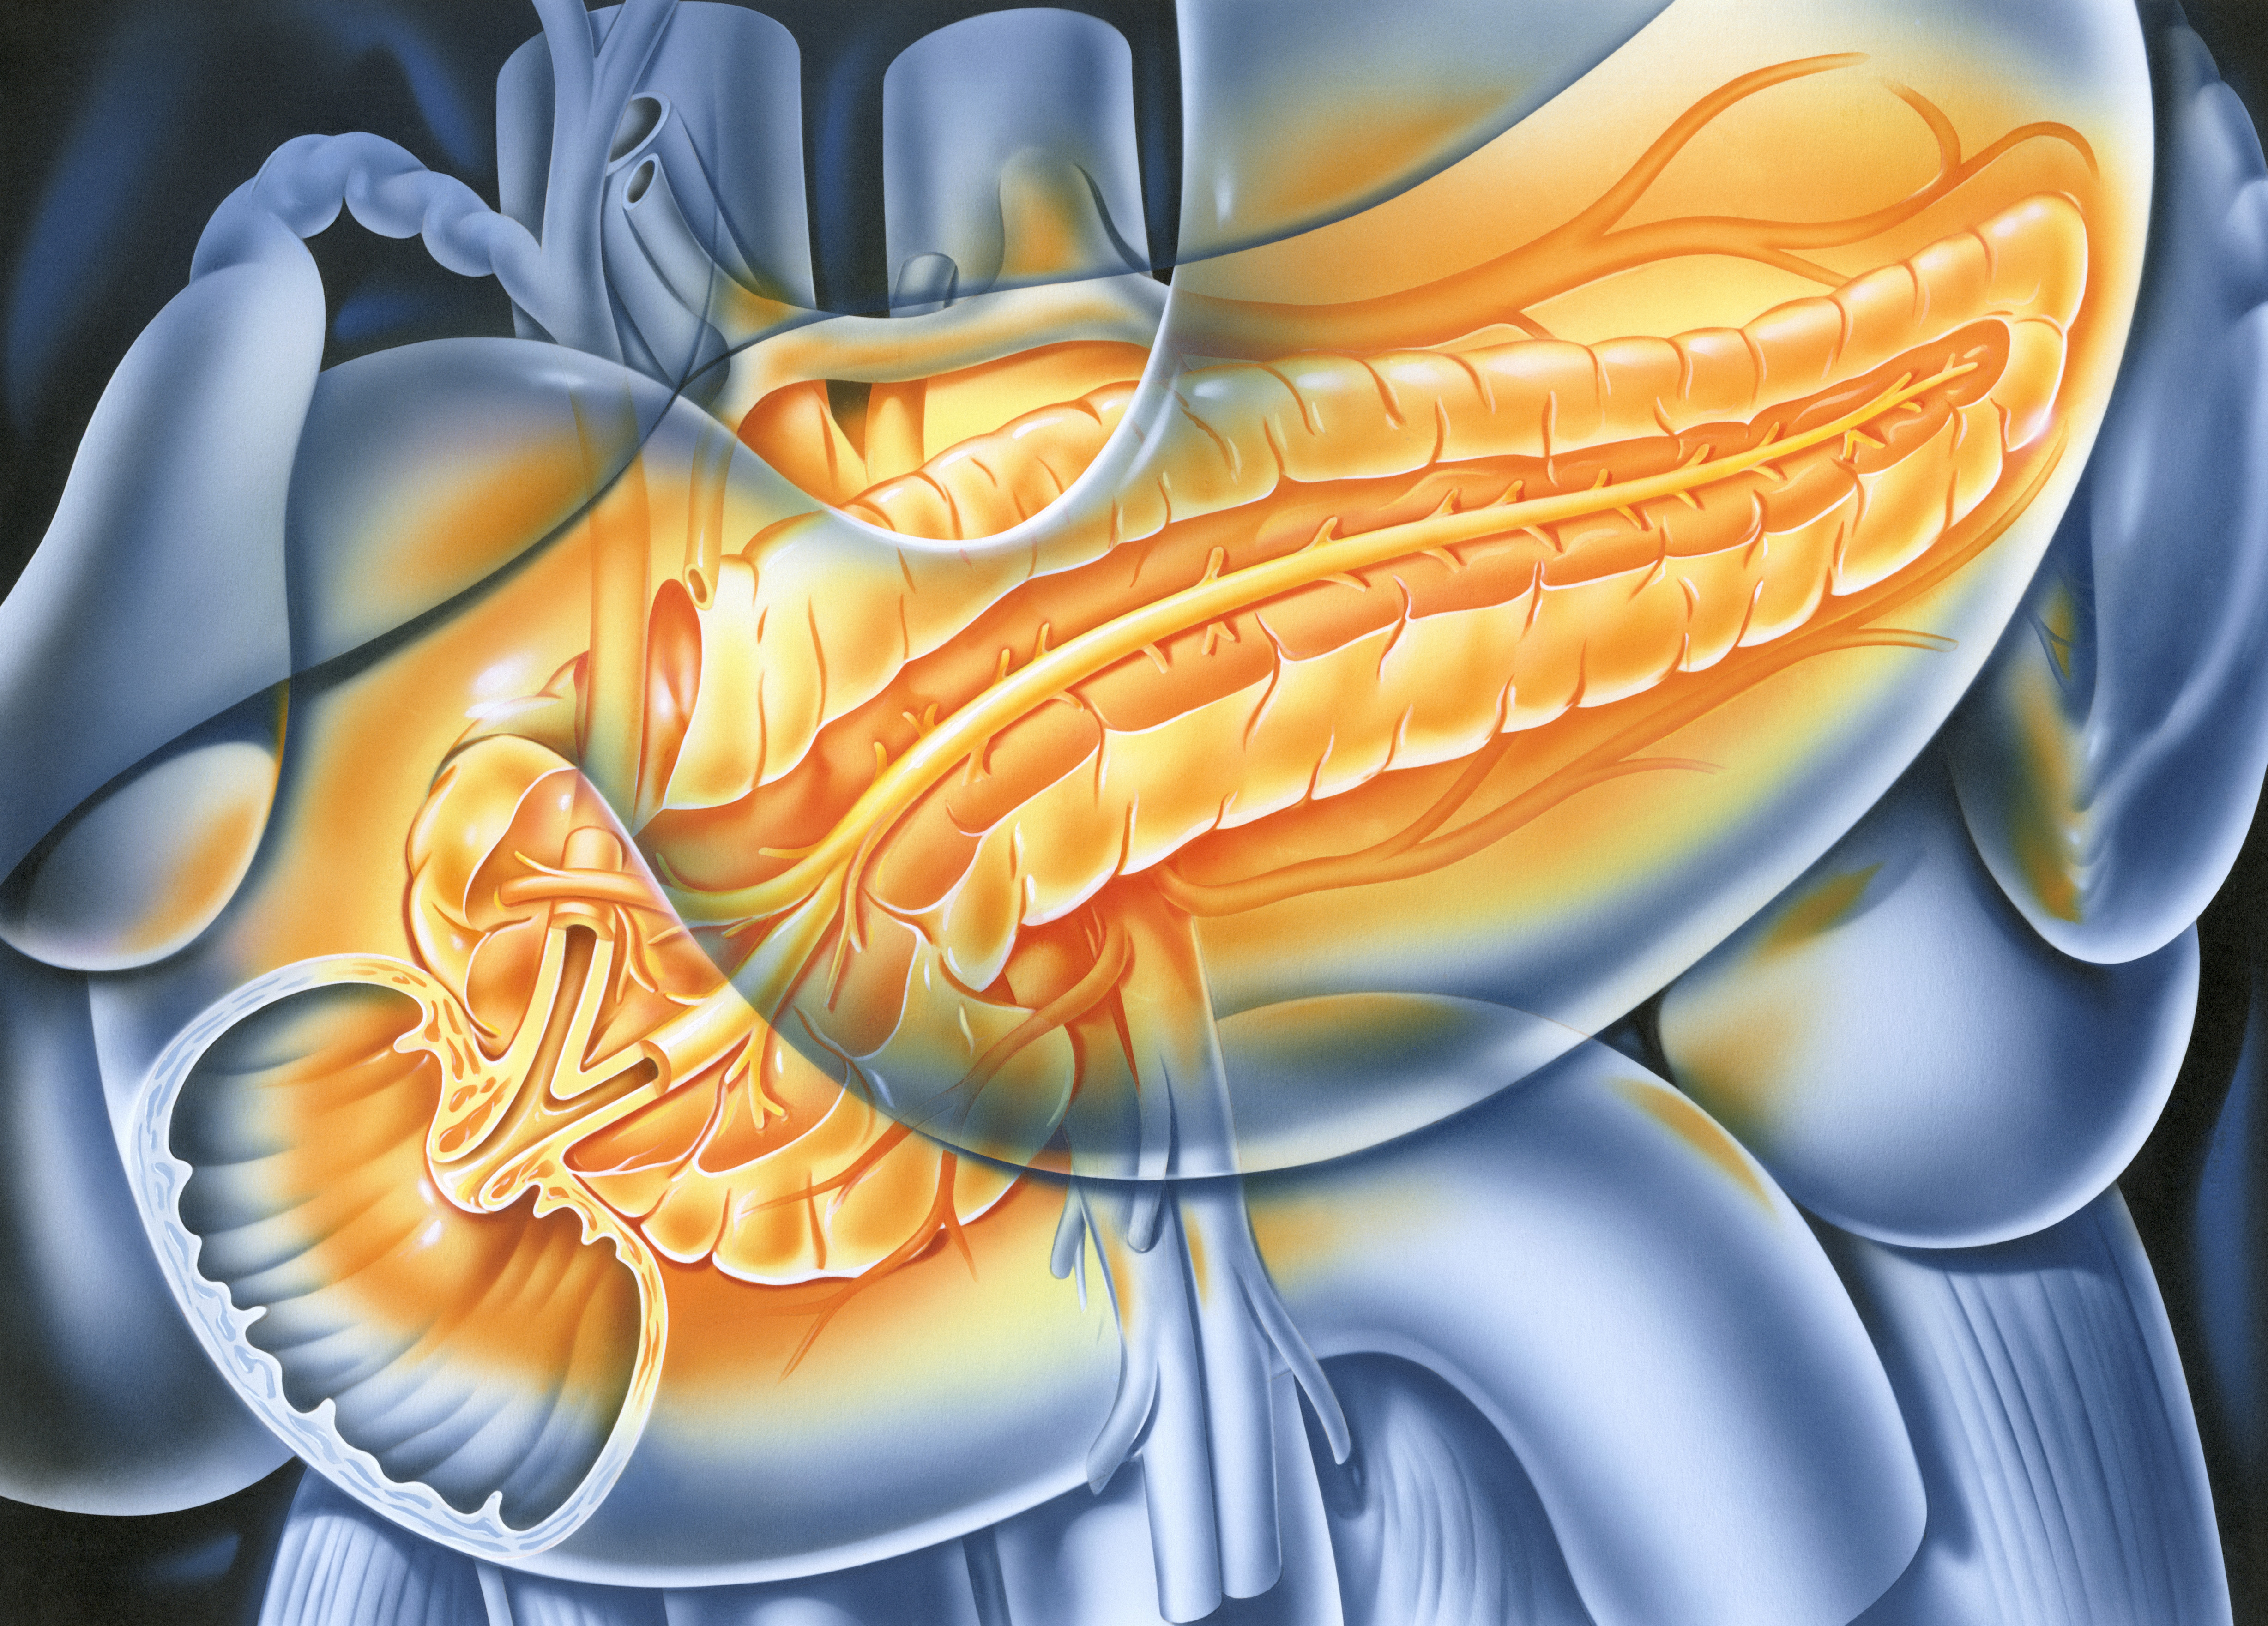

췌장은 머리, 몸통, 꼬리의 세 부분으로 나누어지며, 췌장암은 췌장에 생긴 종양을 뜻하고, 췌장의 머리에서 가장 빈번하게 발생하며, 특히 췌관세포에서 발생하는 췌관선암종이 가장 흔하게 발견됩니다.

- 췌장은 위치적으로 복부 깊숙하게 자리를 잡고 있고, 췌장의 머리와 꼬리 부분은 잘 보이지가 않아 보이지 않는 곳의 암세포를 발견하기가 쉽지 않습니다.

특히, 인체 깊숙히 위치한 췌장, 그리고 그 주변의 복잡한 해부학적 구조, 절제 후 어렵고 정교한 문합을 시행해야 하는 췌장절제술에 절개를 최소화하고 확대된 시야, 안정된 움직임을 가능하게 하는 로봇수술은 개복 수술에 비해 수술 후 환자분의 통증을 줄여주고 합병증 발생률을 낮춰 회복을 빠르게 하고 조기에 사회로 복귀시키는 방법이라 할 수 있습니다.